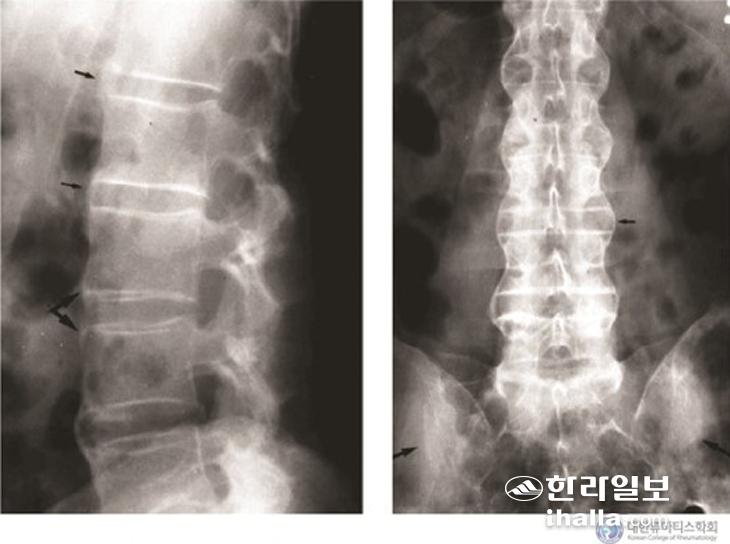

고관절염과 어깨관절염은 25~35%의 환자에게서 대체로 질병 초기에 나타난다. 강직척추염의 가장 특이한 소견은 뼈인대골극의 형성으로 인한 척추 운동능력의 소실이며 이로 인해 요추의 전압과 측방 굽힘, 펴기의 제한 및 흉곽 확장 제한이 나타난다.

<강직척추염의 진행과정>

질병의 경과는 다양해 경도의 강직과 방사선학적으로 뚜렷하지 않은 천장관절염만 있는 환자부터 전체 척추가 융합되고 양측 고관절염 및 말초 관절염과 관절 외 증상이 모두 있는 환자까지 다양하다. 40% 정도의 환자에서는 피부 등을 침범하는 관절 외 증상도 발생할 수 있는데, 증상 중에서는 급성전포도막염이 가장 흔하다. 보통 한쪽만 침범하는 경우가 많고 충혈, 통증, 광선공포증, 눈물 증가 등의 증상이 있다. 약 60%의 환자에서 대장이나 회장에 염증 소견이 있으나 보통 증상은 없다. 하지만 5~10%의 환자에서는 실제로 염증장질환이 발생한다.

강직척추염이 의심되는 경우 유전자 HLA-B27, 염증검사, X-ray, MRI 등의 검사를 하게 된다. 강직척추염은 유전자 HLA-B27과의 연관성이 높고 이것이 발병기전에도 관여하는 것으로 알려져 있다. 강직척추염의 유병률은 HLA-B27의 유병률과 비례하는 것으로 알려져 있고 한국과 일본은 대략 4% 정도이다. HLA-B27양성인 사람의 1~6%만이 강직척추염이 발생하지만 강직척추염환자에서 HLA-B27양성률은 90% 정도로 높다. X-ray상에서의 변화는 병이 어느 정도 진행이 돼야 나타나기 때문에 최근에는 관절손상이 발생하기 전 조기에 진단해 치료를 하기 위해 MRI를 시행하고 있다.